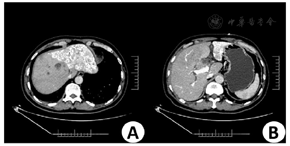

3月12日上腹部增强CT提示肝门部胆管癌可能(图1)。3月13日B超提示肝门部至胆总管上段占位,考虑肿瘤伴胆管受侵可能。3月16日上腹部增强MR提示肝门部胆管癌伴胆道梗阻可能(图2)。3月12日实验室检查示,AFP为8.1 ng/ml,CEA为1.61 ng/ml,CA50为68.76 IU/ml,CA19-9为80.89 IU/ml,ALT为126 IU/L,AST为76 IU/L,TBIL为77.7 umol/L,DBIL为62.5 umol/L。